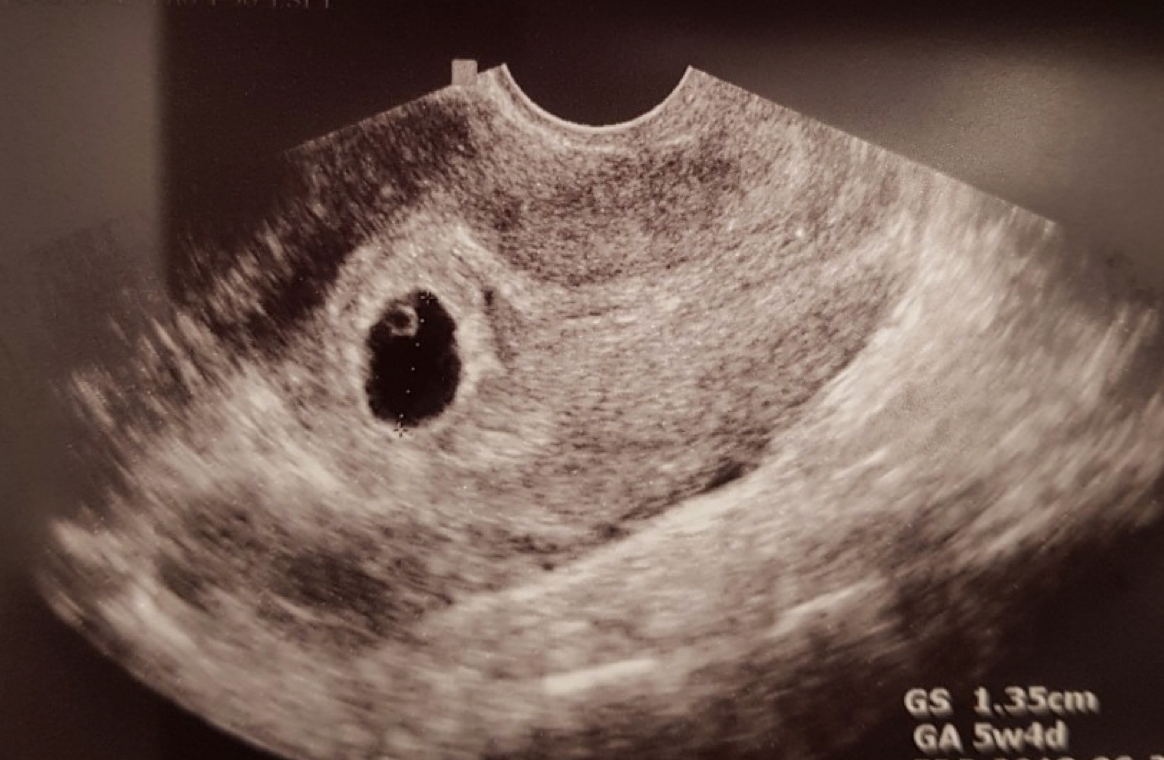

아내가 임신을 했다.

작은 동그라미 하나가 우리의 아이라니.. 실감이 나지 않았다.

두 손 꼬옥 잡고 찾아간 산부인과에서 임신 확정 진단을 받고 난 뒤,

우리는 공식적으로 엄마와 아빠가 되는 첫 걸음을 시작했다.

너는 눈코입하나 없는 작은 동그라미 점의 모습으로 찾아온 순간부터